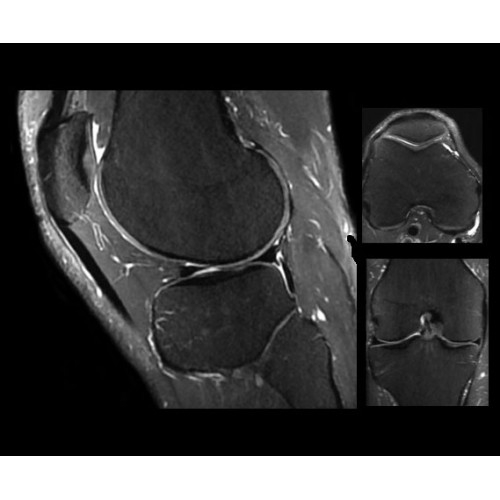

Компания GE Healthcare представляет революционную, полностью интегрированную систему SIGNA PET/MR1, в которой сочетаются времяпролетная технология (TOF) и возможности напряженности магнитного поля 3.0 Тл. Мы поможем вам поднять исследования на более высокий уровень. SIGNA PET/MR позволяет достичь впечатляющей точности и скорости исследований, а благодаря новейшей технологии реконструкции Q.Clear2 качество изображений улучшается в два раза. Кроме того, в систему включен полный набор клинических приложений и гибких катушек для проведения любых видов исследования, открывая для вас возможности визуализации, о которых вы даже не догадывались.

Система SIGNA PET/MR предлагает впечатляющие клинические возможности и открывает доступ к наиболее полным пакетам программных приложений.

Стандартный пакет приложений SIGNA Works позволит вам достичь желаемых результатов в клинической практике благодаря набору высокоэффективных средств визуализации. Программные приложения, входящие в состав данных клинических пакетов, включают широкий спектр контрастов, функции обработки 2D- и 3D-данных, а также возможность коррекции артефактов движения. SIGNA Works предоставляет набор инструментов, необходимых для проведения эффективного клинического исследования.